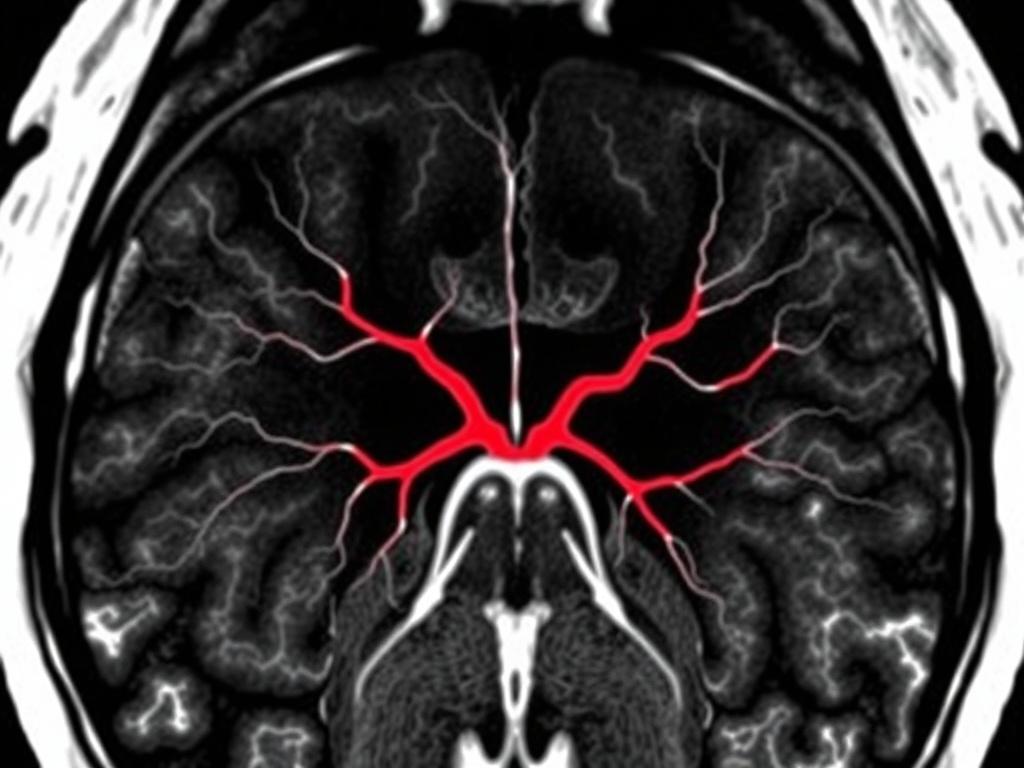

- МР-ангиография – продвинутый метод, который позволяет создавать картины сосудистой системы без инвазивных вмешательств. Обычно используется для изучения состояния артерий и вен в реальном времени.